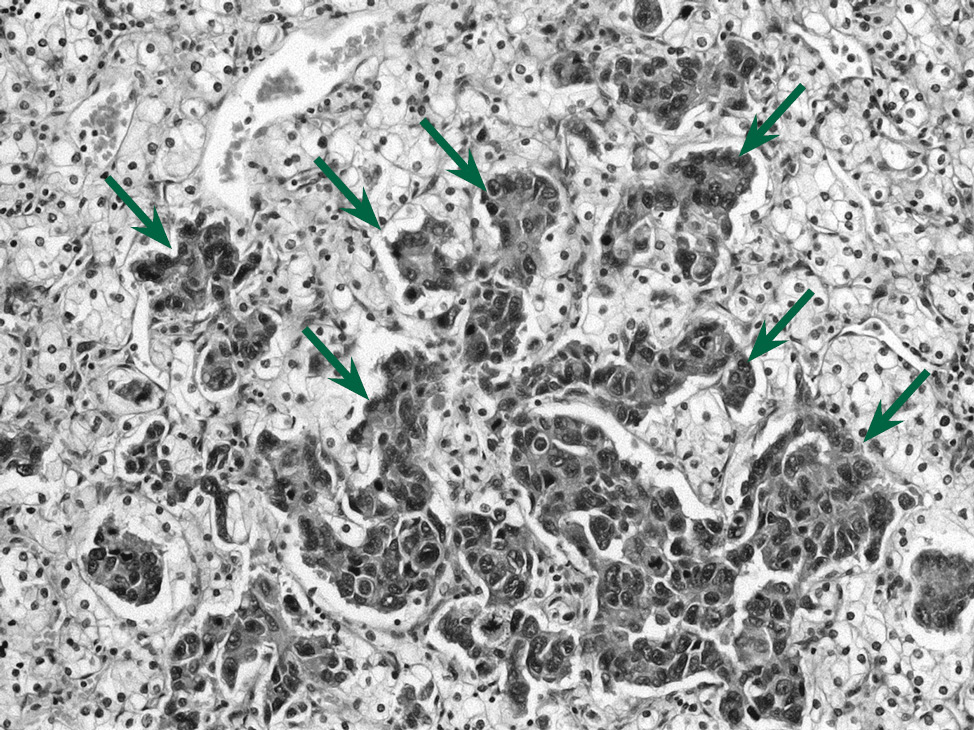

Aim of the study is to demonstrate a unique case report: synchronous malignant tumors of the breast and kidney with tumor to tumor metastasis.

Materials and methods. The analysis of medical history and the pathology study of surgical material using histological and immunohistochemical methods was carried out.

Results. Clinical observation of metastasis of triple-negative breast cancer in a synchronous renal cell carcinoma of the kidney in a 59-year-old woman has been described. Tumor to tumor metastases are diagnosed by a remote kidney with a neoplasm, hematuria, anemia, and thrombocytopenic syndrome manifested in the clinic.